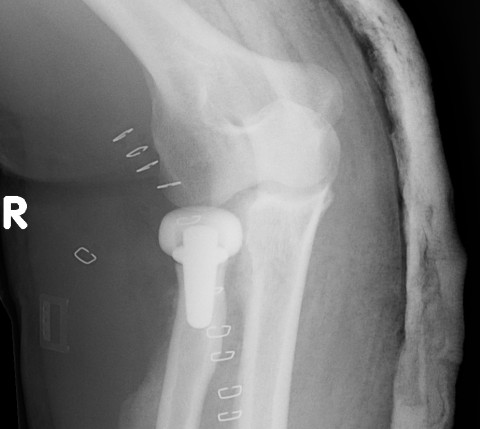

![]() |

Overstuffing

| Lesser sigmoid notch | Symmetry of ulnohumeral joint |

|---|---|

|

Radial head shoulder articulate with lesser notch

Ensure no gapping of lateral ulnohumeral joint |

- cadaveric study

- increased medial ulno-humeral joint line gapping with overlengthening of 6 or 8 mm

- increased lateral ulno-humeral joint line gapping with overlengthening of 2 mm